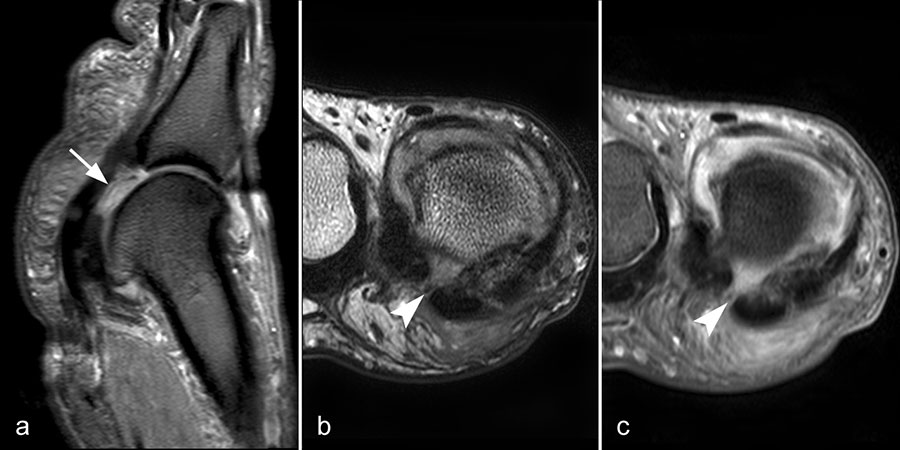

Rupturen ereignen sich am häufigsten an den distalen Insertionen der Metatarsophalan­gealgelenke (Abb. 5), etwas seltener auf Höhe der Metatarsaleköpfchen. Die Läsionen können sehr umschrieben sein, quer durch die gesamte plantare Platte reichen und sich sogar bis in die Kollateralbänder fortsetzen 1. Rupturen der plantaren Platte finden sich am häufigsten an der zweiten Zehe, die dritte Zehe ist etwas seltener betroffen. An der vierten und fünften Zehe sind die Läsionen sehr ungewöhnlich. Rupturen der pantaren Platte führen häufig zu einer ausgeprägten Weichteilreaktion, die nicht als Morton-Neurom fehlgedeutet werden sollte (Abb. 6) und zur Ausbildung einer Neo-Bursa führen können (Abb. 7).

Ein Sonderfall stellt die Großzehe dar: Hier verstärken die Sesambeine, das intersesamoidale und die sesamophalangealen Bänder die Gelenkkapsel. Der faserknorpelige Anteil der plantaren Platte distal der Sesambeine ist oft nur sehr dünn. Verletzungen dieser plantaren Kapselstrukturen des Großzehengrundgelenkes werden auch als „turf toe“ bezeichnet

(Abb. 8).